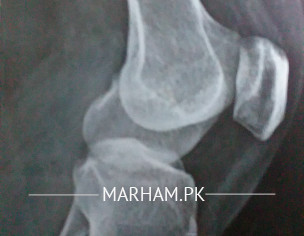

i am having pain in my left knee from almost one year . i am mother of 3 and having difficulty in my routine household work. its painful if i stand for long time or if i sit down while offering prayer. uric acid ,blood sugar, cbc all tests show normal result. this is my recent x-ray report. please guide

was this x ray done in standing position.

if you are overweight, you need to reduce some wright because sometimes more weight on knees causes this pain.

other than this, its difficult to comment on xrays without seeing patients or as other questions.

no i was on x ray bed , my weight is 60kg and height is 5.2